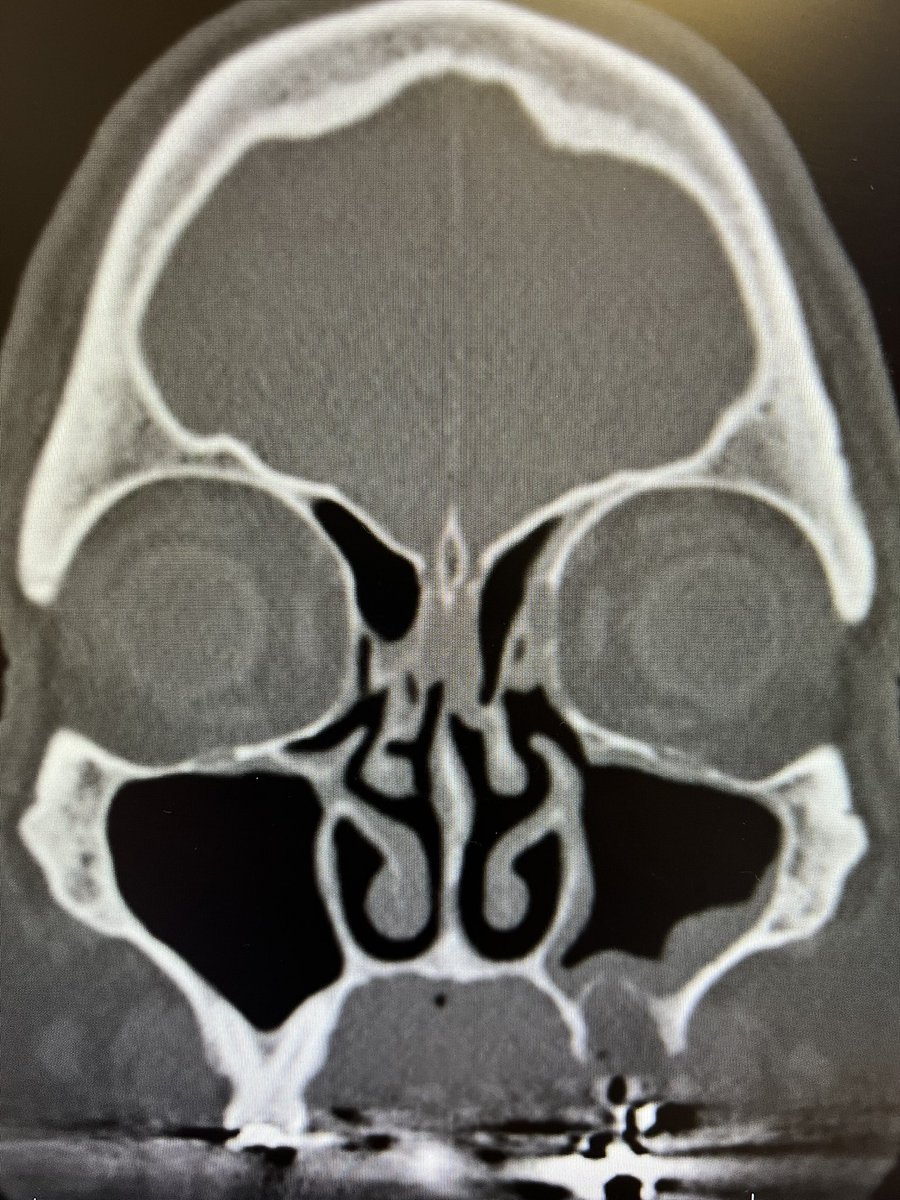

Kevin C. Welch, MD

@igotsinus

Professor Rhinologist, sinus surgeon and skull base surgeon. Wine Guy. WSET II, FWS, Rhône ML, Bordeaux ML #revisionsinussurgery #polyps #sinussurgery